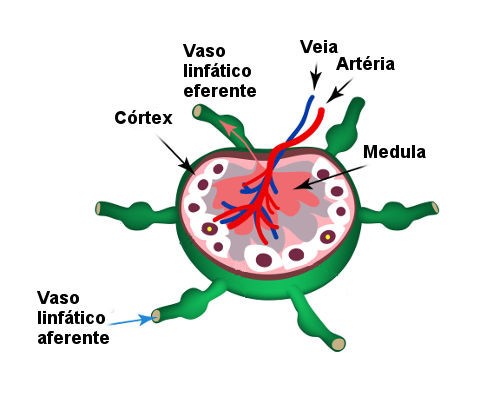

Em resumo, anatomicamente, o sistema linfático é uma rede de órgãos linfoides, linfonodos, ductos linfáticos, tecidos linfáticos, capilares linfáticos e vasos linfáticos.

Estrutura do Sistema Linfático com ênfase ampliada do Linfonodo.

Como vimos no resumo da semana passada, as células dendríticas (DCs) são especializadas na captura e apresentação de antígenos para os linfócitos, e por sua vez, são consideradas uma ponte entre a imunidade inata e a adaptativa, justamente por serem atraídas e ativadas por elementos da resposta inata e viabilizarem a sensibilização de Linfócitos T da resposta imune adaptativa.

Essas, residem em tecidos periféricos, como pele, fígado e intestino, onde capturam antígenos e se tornam ativadas. Após isso, tais células serão direcionadas e migrarão diretamente para os linfonodos regionais, que são responsáveis por processar e apresentar antígenos proteicos ou lipídicos aos LTs (5, 7).

Sabe-se que DCs imaturas são altamente eficientes na captura de antígenos, enquanto as maduras são muito eficientes na apresentação.Os antígenos capturados são processados dentro da célula e apresentados em sua superfície, inseridos em moléculas do MHC. Em geral, antígenos proteicos são apresentados por moléculas MHCs clássicas, de classes I e II (5, 7)

Estrutura Anatômica do Linfonodo.